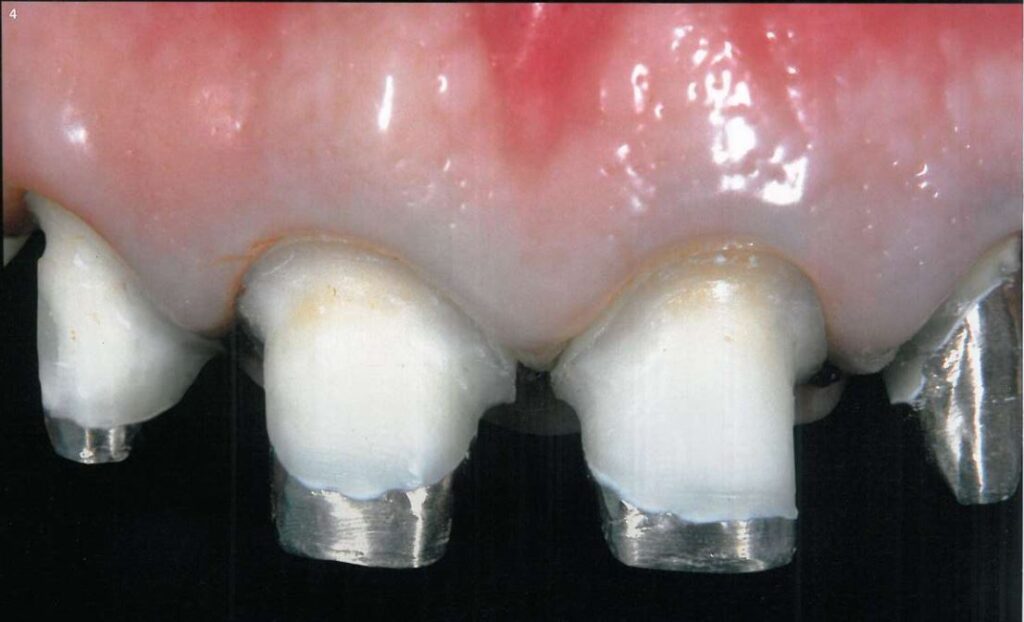

Khi sử dụng kĩ thuật đặt chỉ đôi (2 sợi), thì sợi chỉ với đường kính nhỏ hơn được đặt vào trước tiên. Sợi chỉ đầu tiên này nhằm giúp ngăn ngừa máu và dịch trào lên khi rút sợi chỉ thứ 2 ra (H3,4).

Hình 5 minh họa sợi chỉ thứ nhất được đặt vào khe nướu, tách nướu rời xuống khoảng 0.5 – 1 mm nhằm ngăn sự tiếp xúc của đầu mũi khoan với biểu mô nướu trong quá trình điều chỉnh đường hoàn tất.